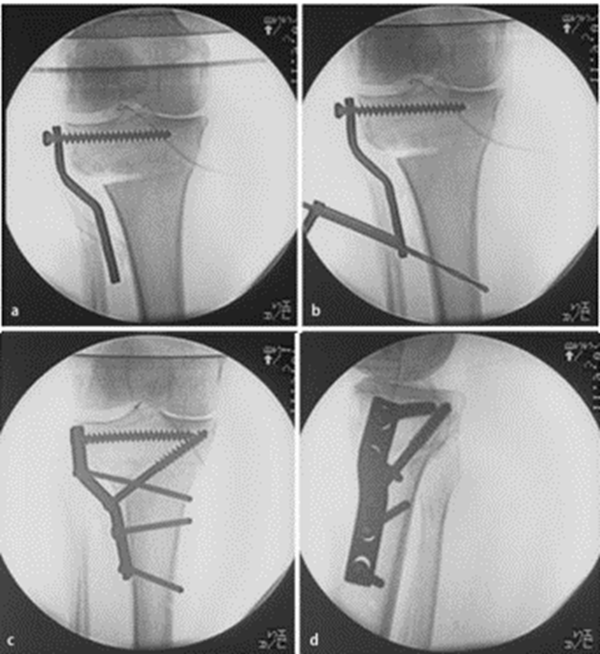

胫骨高位截骨结合外固定支架治疗

Cengiz Sen等治疗53例,取得良好疗效。相对于采用内固定术治疗,外固定支架可避免矫正度数丢失,胫骨近端骨缺失等,可以延缓关节炎进展。

开放楔形截骨,采用不同固定方法,结果显示:外侧合页破坏时,钢板螺钉固定组比骑缝钉固定组、外固定支架组,能够提供更好的稳定性。